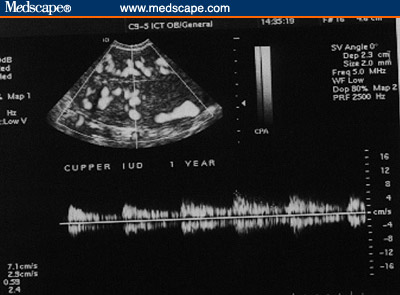

Figure 3. Copper IUD. (3A, Sagittal view [Note the

echogenicity of the device throughout its length)]; 3B, Transverse

view.)

Figure 4. Copper IUD. Subendometrial flow. (4A, 1 month post

insertion; 4B, 1 year post-insertion [Note the rich flow even a year

post insertion of the IUD.])